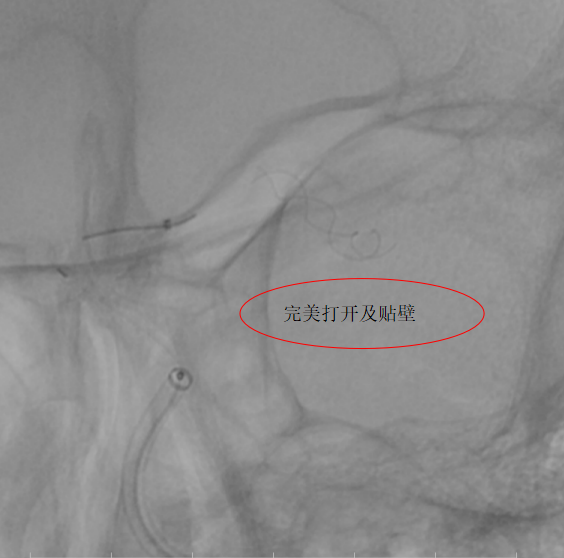

第二例患者为左侧大脑中动脉动脉瘤,该部位血管解剖结构复杂,对手术的精准度要求极高。团队使用血流导向装置,支架完美打开及贴壁,患者术后3天顺利出院。